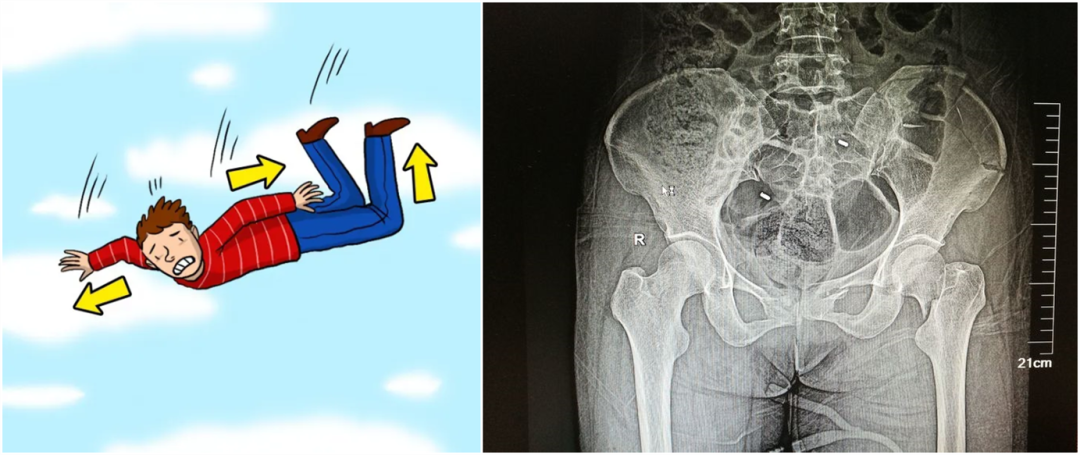

外傷性骨折

從暴力的大小來看,還可以細(xì)分為高能量的損傷和低能量的損傷。比如說,如果是車子撞的,從高處墜落,通常會(huì)造成高能量的損傷,而普通的跌倒造成的骨折,一般不太嚴(yán)重,可以說是低能量的損傷。

【醫(yī)療科普】:不穩(wěn)定性骨折影像

不穩(wěn)定性骨折